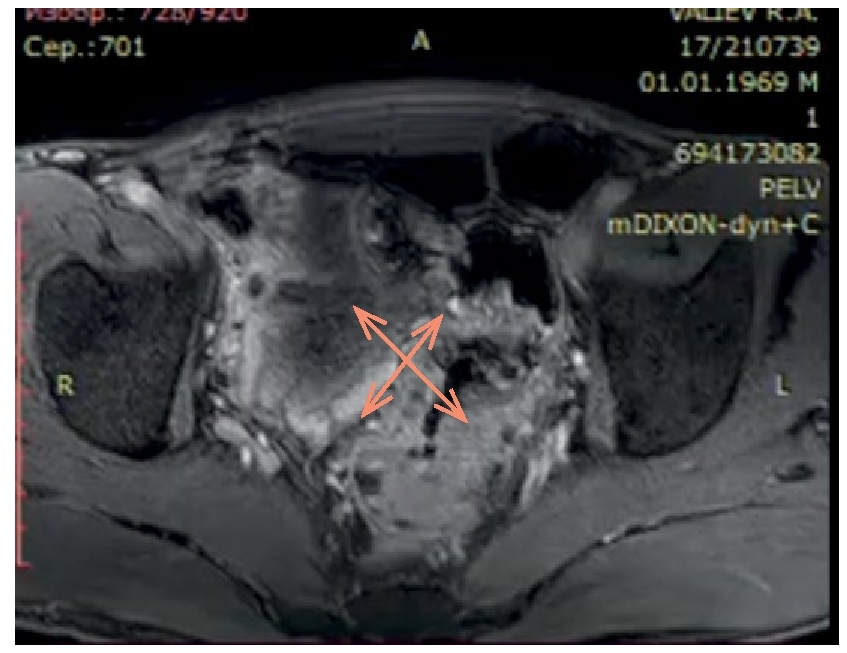

Findings of laboratory examinations: the level of carcinoembryonic antigen (CEA) was 26.07 ng/ml, and the level of cA 19-9 was 3.7 units/ml. Findings of magnetic resonance imaging (MRI) of the pelvic organs with contrasting (Fig. 1): in the rectum, at the height of 95 mm from the anus and higher, at a length of approx. 80 mm, there is a deformation and an uneven infiltrative thickening of the walls up to 20 mm that affected all layers, with a moderate obstruction of the bowel lumen; with intravenous contract administration, it accumulated the contrast in an unevenly intensive way. In the affected area, the outer contours of the bowel are uneven and indistinct, with signs of invasion to the mesorectal fascia. Pelvic vessels have no pathological changes. Enlarged mesorectal lymph nodes up to 11×7 mm are visualized. Conclusion: locally advanced rectum cancer, metastases to mesorectal lymph nodes; benign hyperplasia of the prostate.

Figure 1. MRI of the pelvis. Picture of locally advanced rectal cancer (indicated by arrows).

Рисунок 1. МРТ малого таза. Картина местнораспространенного рака прямой кишки (указано стрелками).